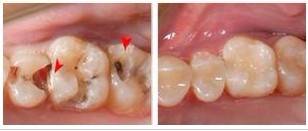

蛀牙是我们日常生活中比较常见的一种牙齿疾病,而多数蛀牙在童年时期都已经形成,而小孩子的蛀牙很多时候并没有收到家长的足够重视,总觉得迟早会换牙,换完牙就好了。在此贝臣齿科医生提醒:其实蛀牙的危害非常大,不能因为换牙而置之不理,一旦发现蛀牙就要及时进行治疗。 >>>点击免费咨询,或者拨打24小时齿科健康热线0591-88681777咨询,贝臣齿科为您解答!

根据贝臣齿科医生介绍,由于补牙材料不同,价格也不同,牙齿受蛀牙侵害的程度不同,价格也不同。牙齿损坏的程度一般按牙洞的大小来定义,一般的口腔科补牙同一种补牙的材料,医生会根据牙洞的大小来定补牙的价格,所以如果你发现自己有了牙洞,一定要尽早治疗,否则牙洞发展的越来越大,补牙的价格也越来越贵。 >>>点击咨询,详细了解关于蛀牙!

如果牙齿坏到了一定程度,就不是单纯的补牙就可以了,需要根管治疗,其价格也不会很贵,根据牙位不同和地区差异。前牙一般只有一个牙根,操作起来也比较简单,收费比较低,后牙牙根比较多,有的时候能达到三到四个牙根,而且操作起来也比较困难,所以这样的补牙的价格就比较高了。

贝臣齿科医生提醒:无论蛀牙是通过一般简单的补牙,还是通过根管治疗后再补牙,都会有不同的补牙材料供顾客选择。儿童的补牙材料相对于成人补牙要低廉。成人的补牙材料多为树脂材料,价格比较贵,分为国产和进口的材料,又根据其特性分为许多种,所以价格也不同。

蛀牙对我们的牙齿还是有很大的影响,尤其是严重的牙痛让人难以忍受了。牙齿内部神经是多罪名的,为了避免造成牙齿疼痛,还是要尽早进行治疗的。 >>>还有不明白的,点击免费咨询,或者拨打24小时贝臣美牙热线0591-88681777咨询,贝臣齿科医生为您解答!